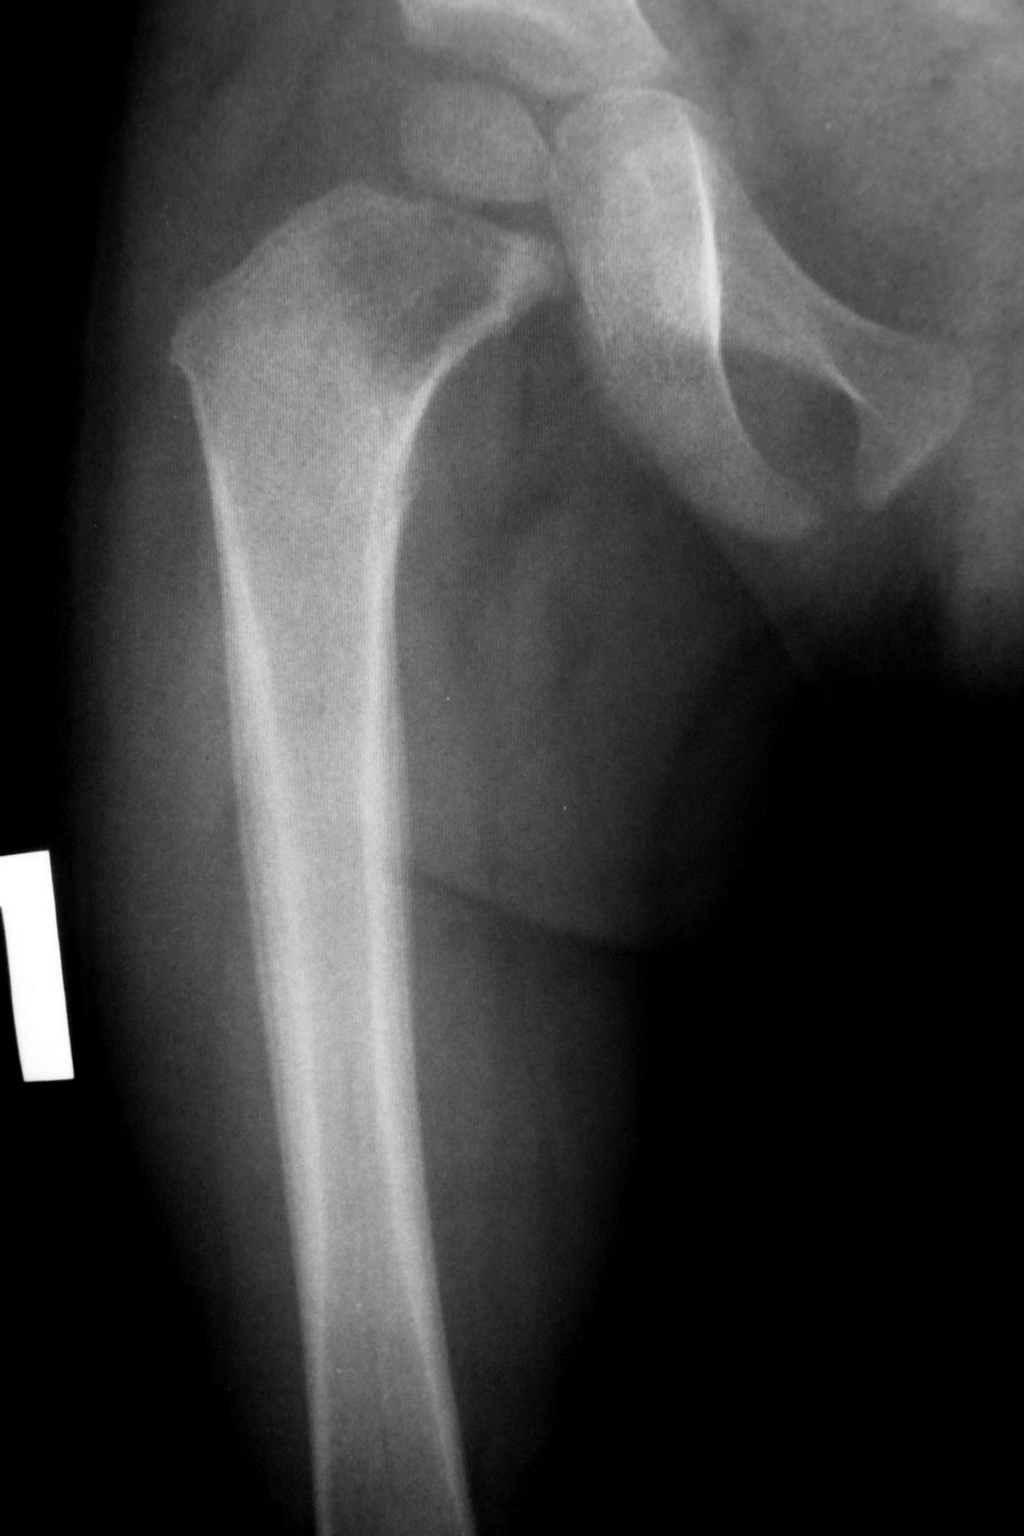

- рентгенологическое обследование – оно имеет наибольшее значение в выявлении патологического перелома бедренной кости. Делают снимки в двух проекциях, на них выявляют линию перелома, смещение отломков (если оно имеется);

- компьютерная томография (КТ) – привлекается в спорных случаях. Компьютерные срезы помогут оценить состояние костной ткани больше, чем рентгенография;

- магнитно-резонансное обследование (МРТ) – помимо оценки состояния костной ткани, поможет проанализировать состояние мягких тканей в области повреждения;